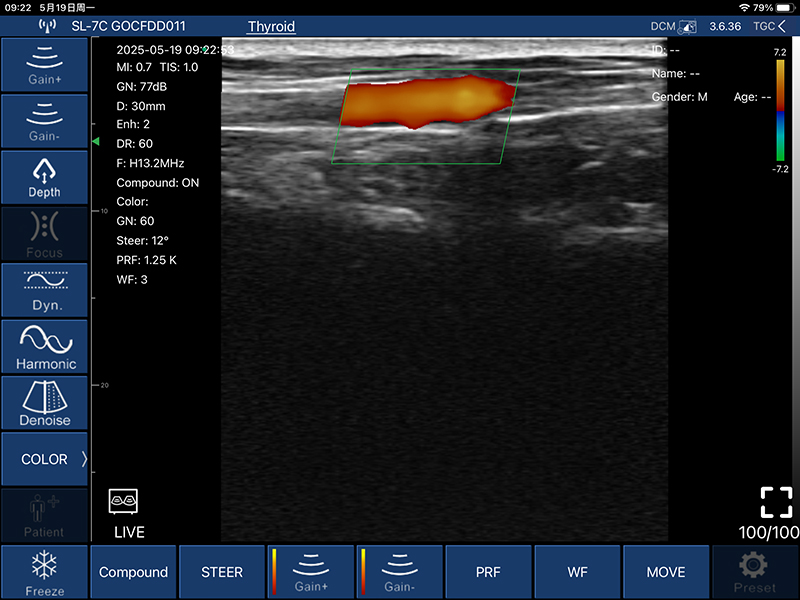

• COLOR模式:

偏转角度:-12/-7/0/7/12度

PRF:≧4组

壁滤波: 0-15

彩色增益:0-100